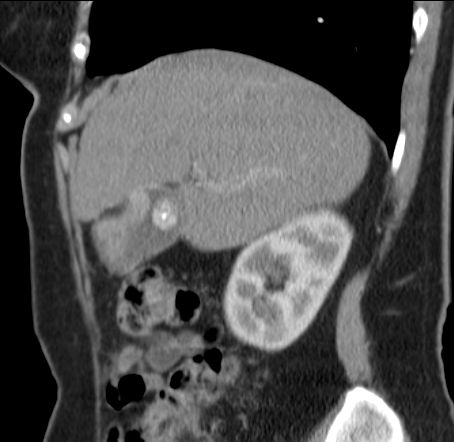

89-jährige Frau mit Infektzeichen. Zunächst sonographisch Verdacht auf Gallenblasenempyem. Im CT ein Gallenblasenkarzinom mit Leberinfiltration. Wegen Alter und AZ palliative Versorgung. | ||